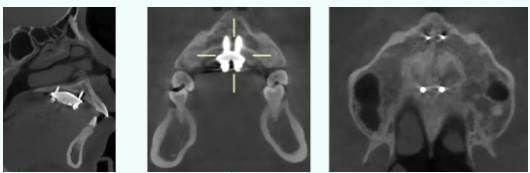

▲图丨微种植支抗钉植入后

上颌牙弓狭窄、横向宽度发育不足是常见错畸形问题,在南疆因呼吸道疾病高发呈发病率上升趋势。儿童青少年可通过传统扩弓器改善,但14岁后传统方式效果锐减,成人上颌扩弓曾几乎只能依赖外科手术,且扩弓量受骨裂隙区愈合能力限制。而口腔医院改进优化并申请专利的上颌骨骨性扩弓器(MSE)技术,通过植入4颗大直径、高强度微种植支抗钉,穿通上颌骨腭旁区骨皮质,传递螺旋扩弓器矫形力,精准扩大腭中缝,为青春发育期后及腭中缝闭合的成人患者提供了微创解决方案。